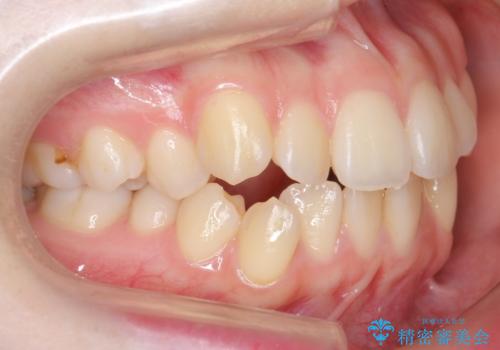

下の八重歯 歯を抜かずに インビザライン治療

- 歯並びのがたつきを主訴に来院。

抜歯してワイヤー矯正という選択肢も提案しましたが、マウスピース矯正で、歯を抜かずに並べてほしいとのことでした。

スペースを確保するために、歯をわずかに削る処置、奥歯を後ろに下げる処置(インプラント矯正)を行っています。